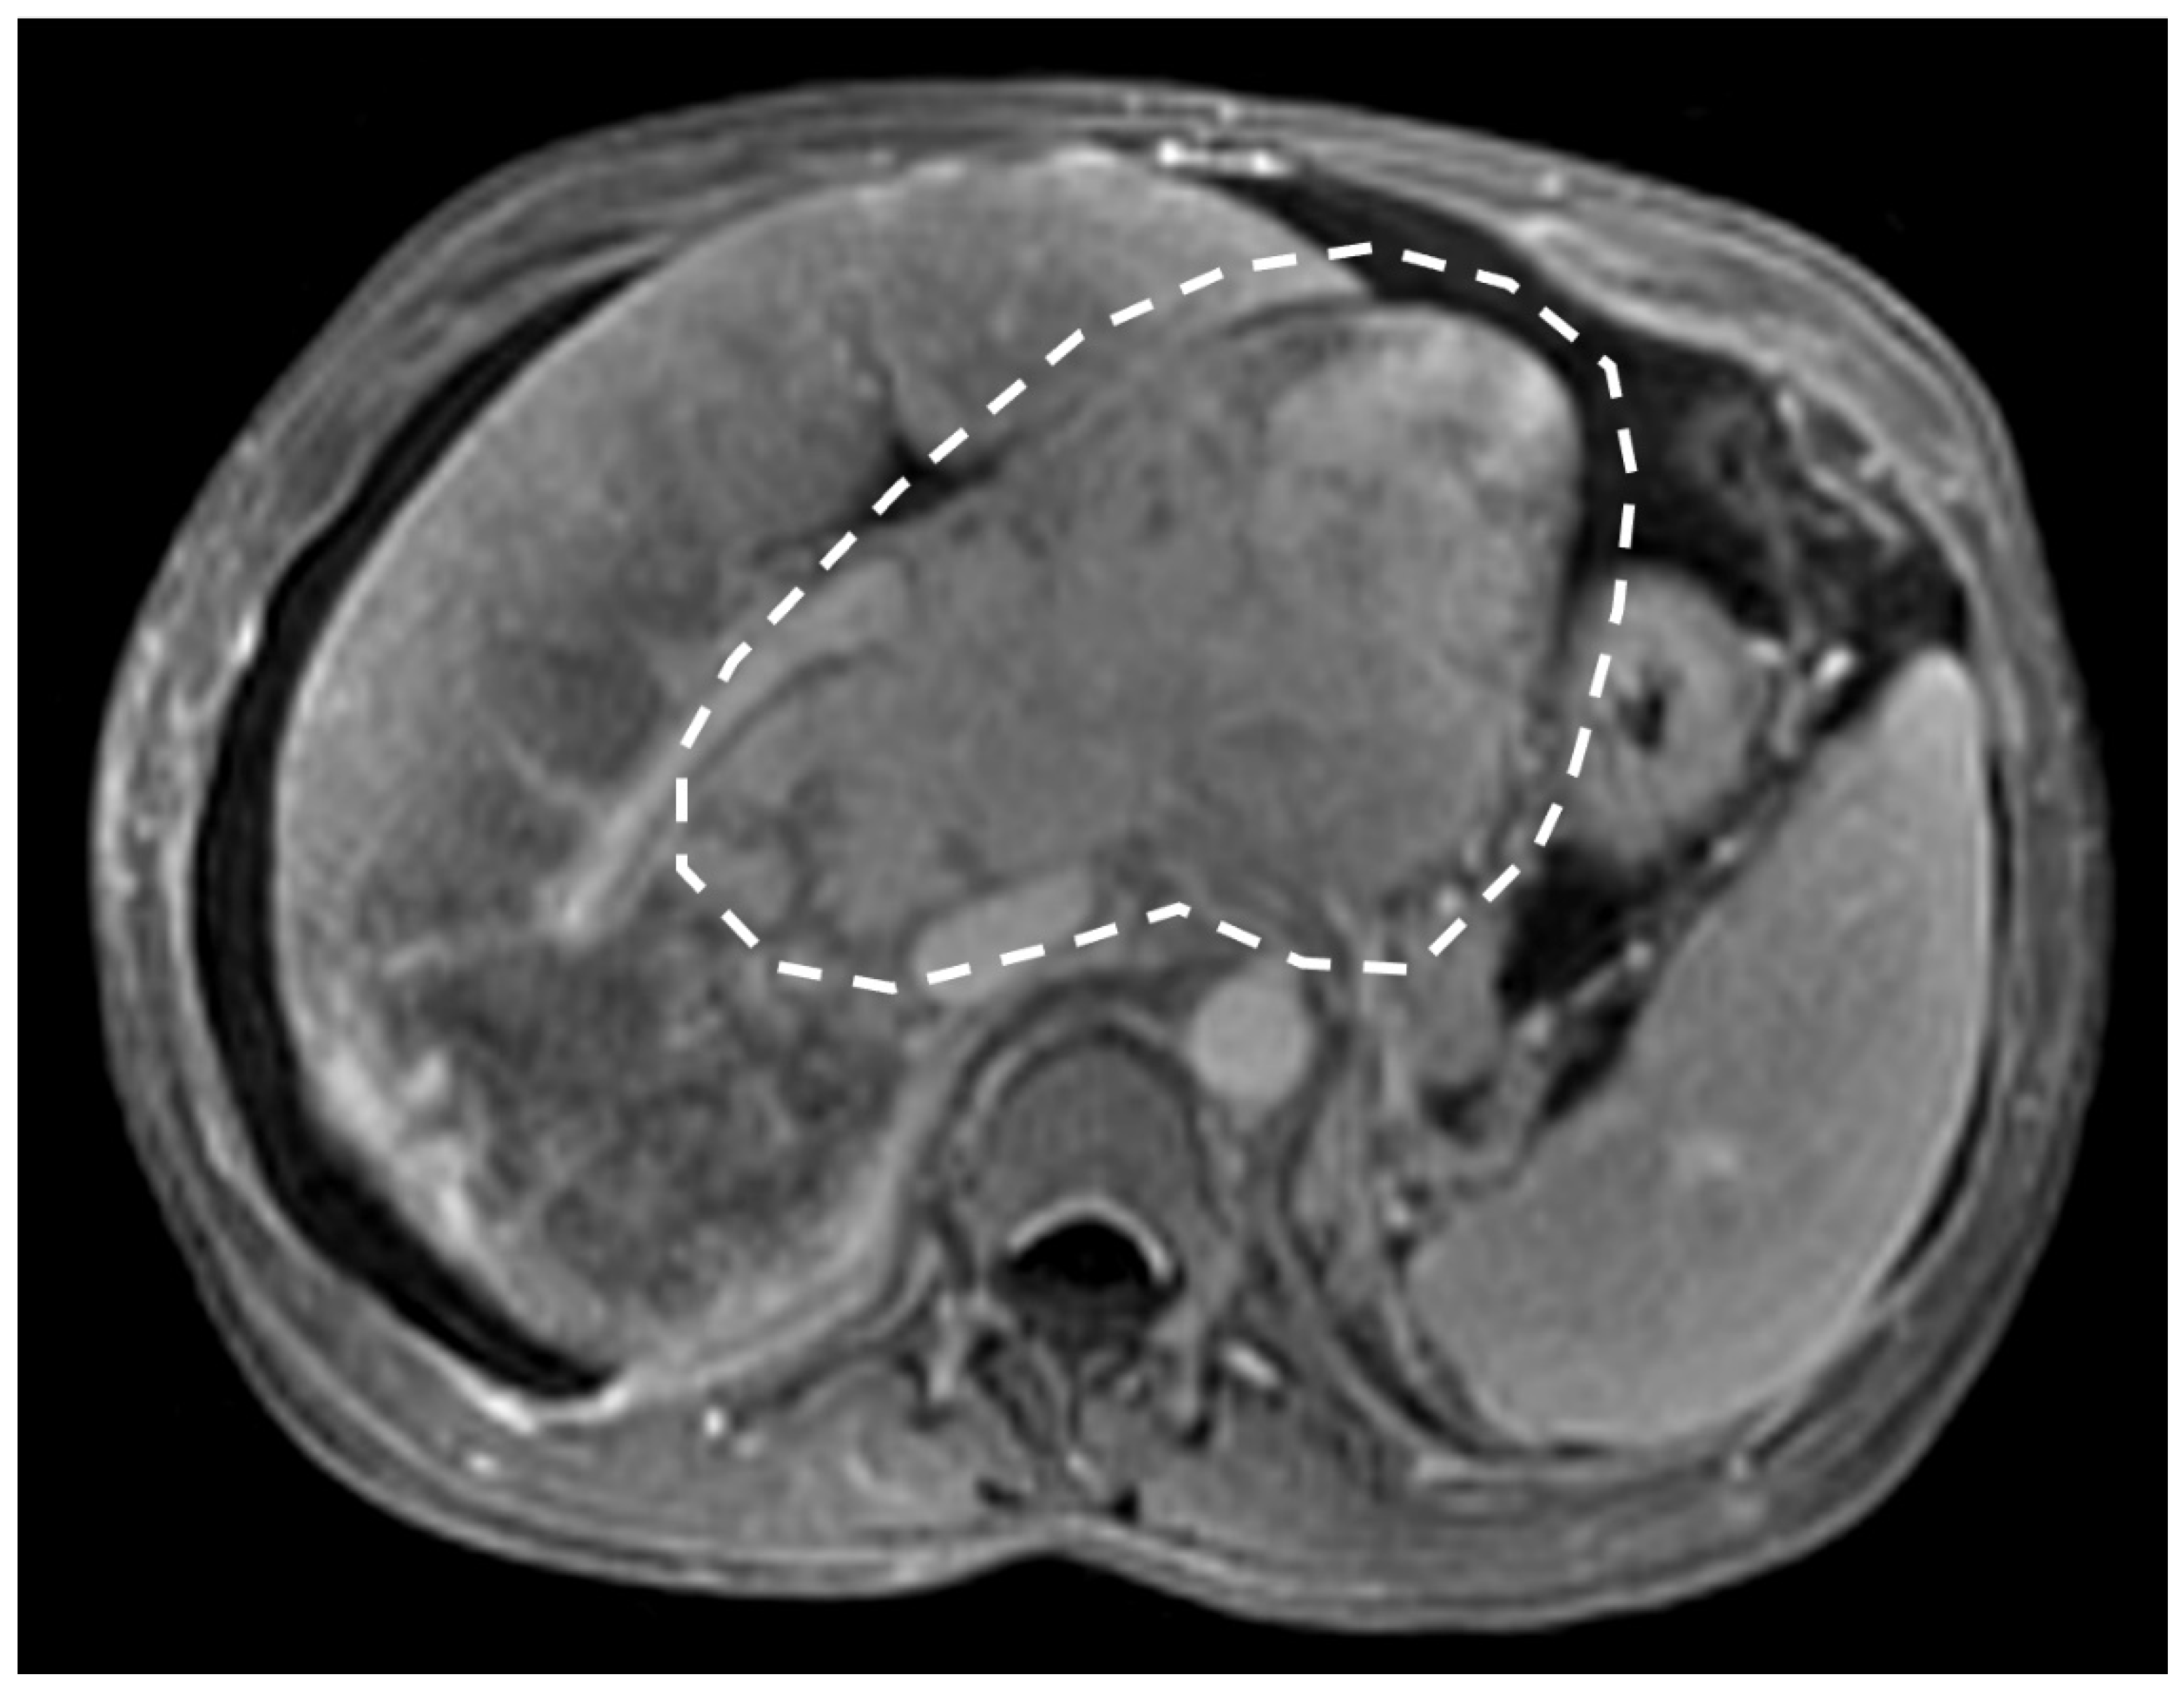

- Indirect signs: non-specific. They represent the consequences of long-standing hepatic venous impairment, including liver parenchymal changes with fibrosis and atrophy of involved segments and hypertrophy of unaffected territories (e.g., caudate lobe hypertrophy). On CT and MRI, centrilobular or sinusoidal congestion, represented as heterogeneous ”mosaic” enhancement after contrast media is also characteristic. Other signs include ascites, portal hypertension, and the presence of benign regenerative nodules, as well as hepatocellular carcinoma [6].

3.2. Computed Tomography and Magnetic Resonance: What to Look For

4. Hepatic Nodules

| CT | Liver morphology alteration Acute phase: “zonal” or “flip-flop” perfusion Chronic phase: “mosaic” perfusion Extra- and intra-hepatic collaterals Site and extension of thrombosis Pre-endovascular treatment assessment Hepatic artery and caudate vein enlargement Hepatic Nodules Ascites and caudal lobe enlargement |

| MRI | Characterization of nodules (FNH-like nodules vs. HCC) T1-w decreased signal in hypoperfused regions, corresponding to high T2-w SI T2*-w flow void corresponding to thrombus. Hypointensity along the occluded vessels |